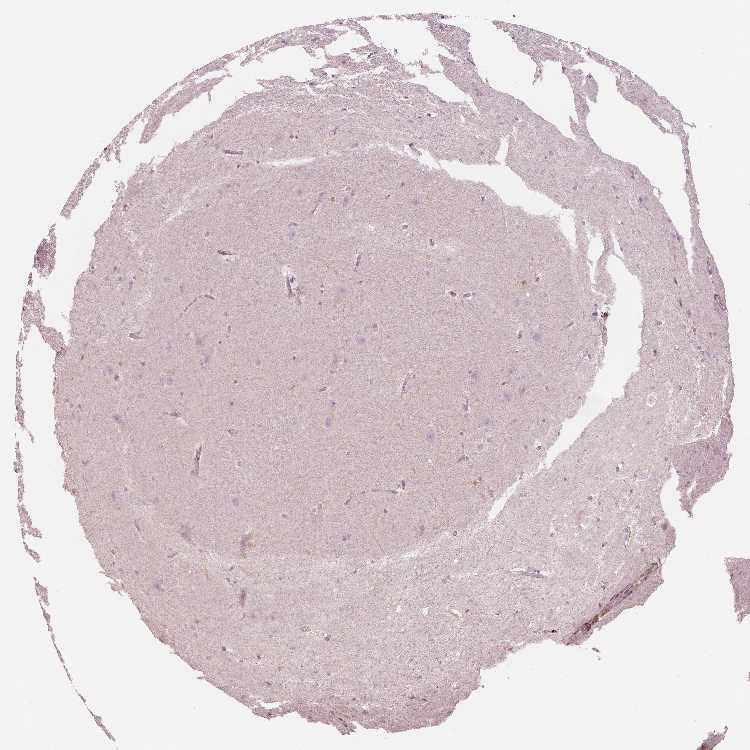

BRAIN HIPPOCAMPAL FORMATION Show tissue menu

HIPPOCAMPAL FORMATION - Expression summary

Protein expression

Hippocampusi

On the top, protein expression in current human tissue, based on all annotated cell types, is reported with the units not detected (n), low (l), medium (m) and high (h). Underneath, protein expression in each annotated cell type are reported using the same units.

Protein expression data is based on knowledge-based annotation. For genes where more than one antibody has been used, a collective score is set.

If knowledge-based annotation could not be performed for a gene, no data is displayed here. View antibody staining data further down this page.

HIPPOCAMPUS - Antibody stainingi

Antibody staining in the annotated cell types in the current human tissue is reported as not detected, low, medium, or high, based on conventional immunohistochemistry profiling in selected tissues. This score is based on the combination of the staining intensity and fraction of stained cells.

Each image is clickable and will lead to virtual microscopy that enables deeper exploration of all samples and also displays staining intensity scores, fraction scores and subcellular localization as well as patient and tissue information for each sample.

Antibody HPA007973Antibody CAB002618Antibody CAB027387Antibody CAB058698Antibody CAB068227Antibody CAB068228

Glial cells Not detectedNot detectedNot detectedNot detectedNot detectedNot detected

Neuronal cells Not detectedNot detectedNot detectedNot detectedNot detectedNot detected